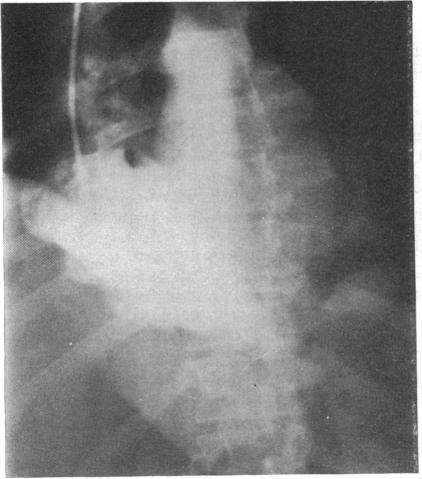

Two cases of angiosarcomas of the heart are described. In one the tumour, which arose from the right atrium, was demonstrated during life by angiography. In the other, diagnosed only at necropsy, the tumour arose from the right ventricle. Both cases illustrate many of the typical features of this rare tumour and the difficulties of antemortem diagnosis.

本文描述了两例心脏血管肉瘤。其中一例肿瘤起源于右心房,生前通过血管造影得以证实。另一例仅在尸检时确诊,肿瘤起源于右心室。这两例病例均体现了这种罕见肿瘤的许多典型特征以及生前诊断的困难。